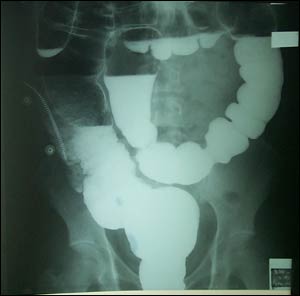

x線平片通過I點設一與PC線相平行的I線,與PC線間的距離為肛提肌群,直腸盲端位於PC線上方者為高位,於二線之間為中間位,超越I線為低位。或者設定M點,即坐骨結節的上2/3與下1/3交接點,在M線上方者為中間位,M線下方者為低位。

但必須注意各種影響因素,如腸道充氣不足、胎便過於粘稠,肛提肌的運動、X線投照角偏斜等均能影響位置的正確性。